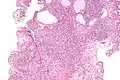

Micrograph of a nephrogenic adenoma. H&E stain.

Nephrogenic adenomas are diagnosed under the microscope by pathologists. Microscopically the tumor shows closely packed small tubular structures in edematous stroma. The tubules show considerable variation in size and shape resembling convoluted tubules of the kidney. The single layer of cells lining the tubules are cuboidal with a scant to moderate amount of cytoplasm. In some areas they may have a hobnail appearance. [2]